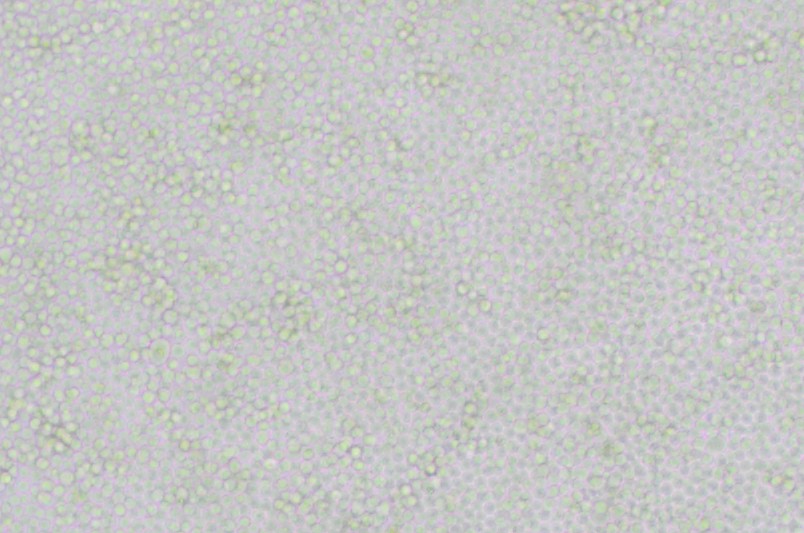

中文名稱 :小鼠淋巴樣瘤細(xì)胞

細(xì)胞簡稱 : P388D 1

細(xì)胞形態(tài) : 淋巴母細(xì)胞樣

生長特性 : 懸浮細(xì)胞

P388D 1細(xì)胞來源于甲基膽蒽誘導(dǎo)形成的淋巴瘤;在LPS和佛波酯的誘導(dǎo)下,P388D 1細(xì)胞可以產(chǎn)生IL-1,還可以產(chǎn)生溶菌酶;可以吞噬酵母多糖和乳膠微球,在抗體依賴的、細(xì)胞介導(dǎo)的細(xì)胞毒系統(tǒng)中有活性。P388D 1細(xì)胞表面免疫球蛋白(sIg)陰性,鼠痘病毒陰性。